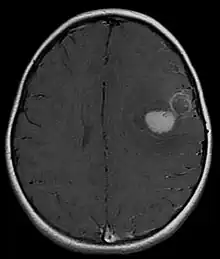

Tumeur neuroectodermique primitive du système nerveux central

Une tumeur neuroectodermique primitive (PNET) du système nerveux central fait habituellement référence à une tumeur neuroectodermique primitive supratentorielle :